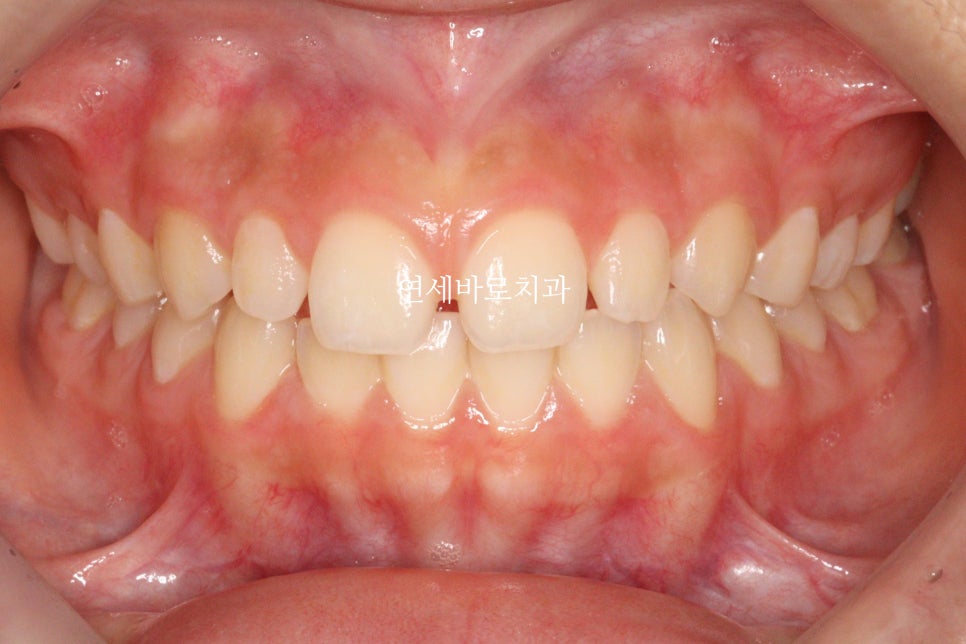

치료가 끝난 당시 모습입니다.

앞니가 듬성듬성 벌어진것이 보기 아쉽네요

이렇게 된 이유는 두가지

왜소치

앞니 형태가 항아리모양 (네모가 아님)

이 환자분도 중심선을 맞추기 위해 고무줄을 함께 사용했습니다.